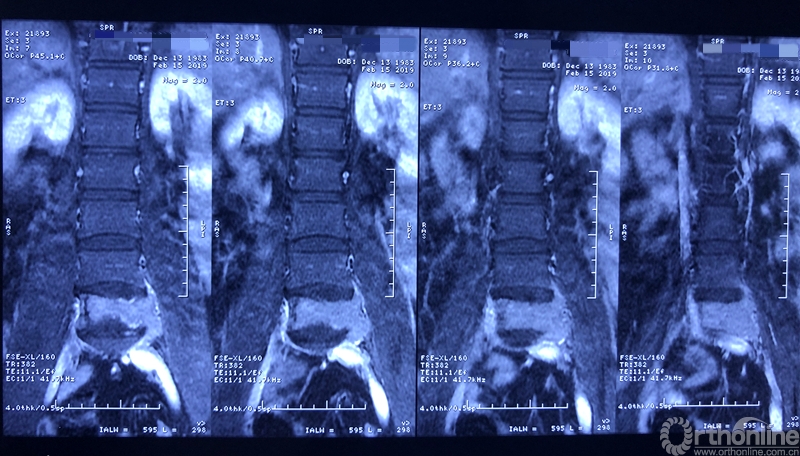

术前X线片